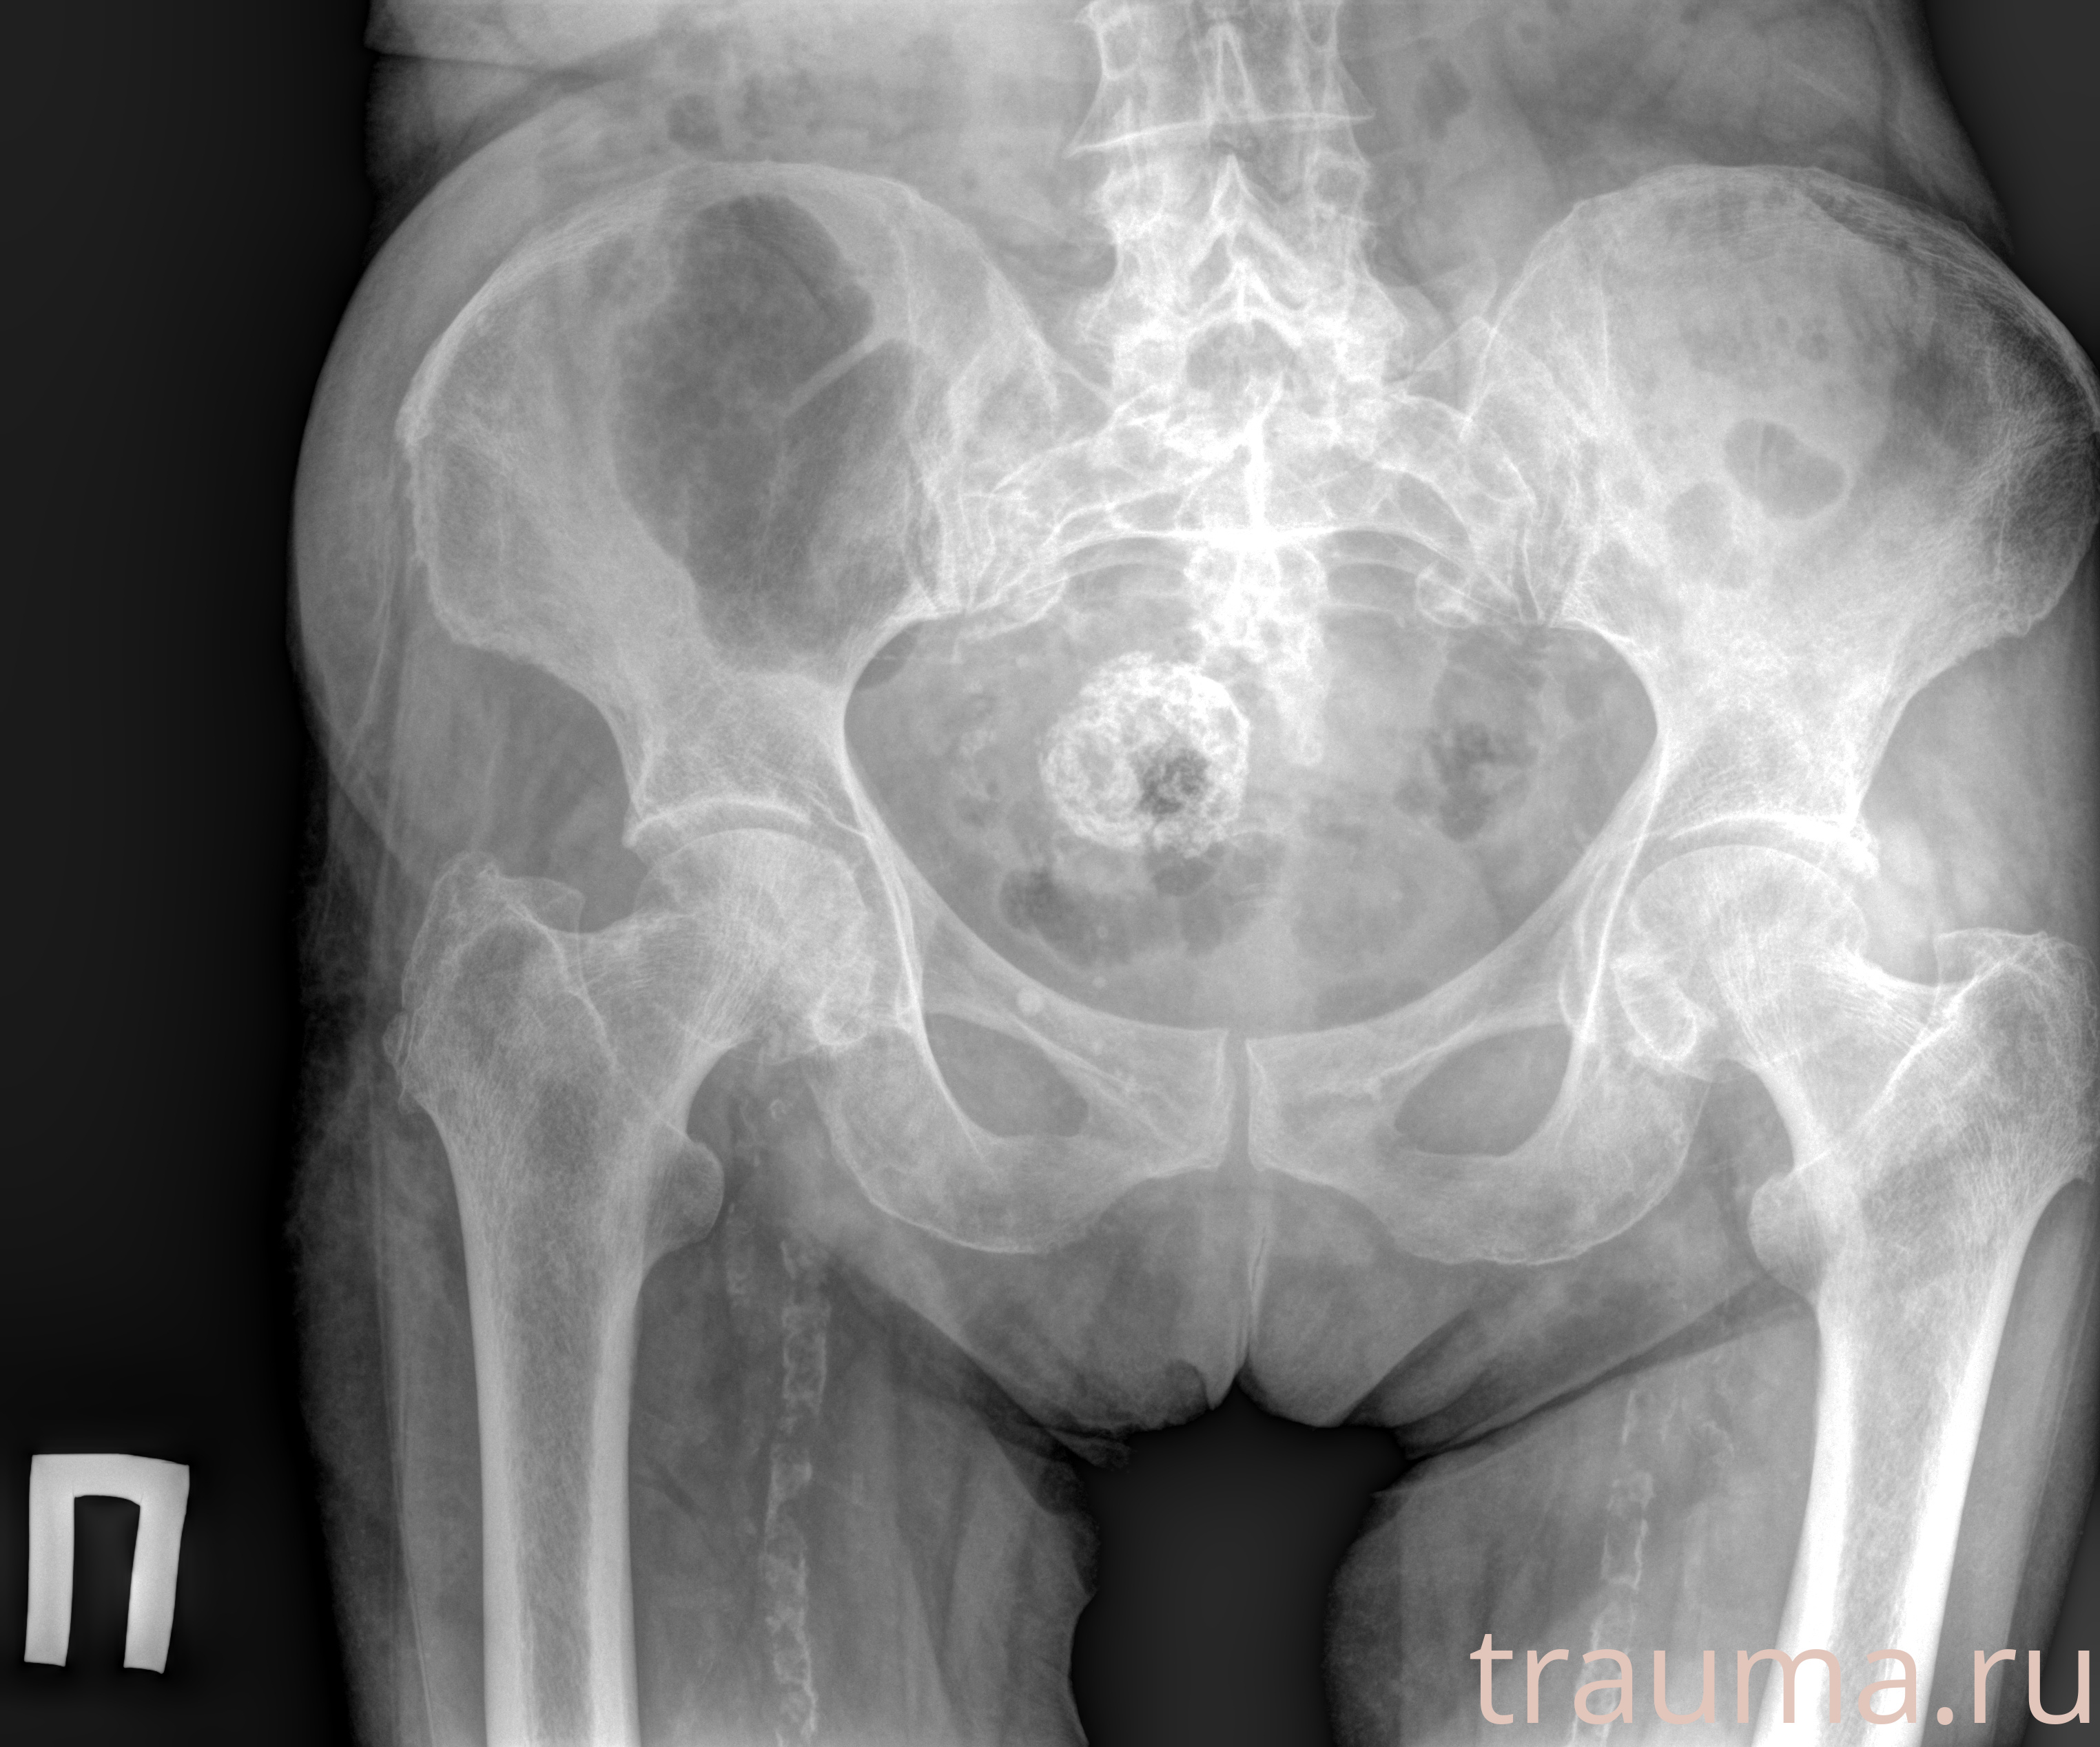

Рентгенограммы

Рентген на дому: по вашему адресу приезжает врач-рентгенолог, травматолог-ортопед с мобильным рентгеновским аппаратом, проводит диагностику травмы или заболевания, делает необходимые рентгенограммы, дает рекомендации по дальнейшему лечению. Получить качественные снимки в домашних условиях возможно благодаря уникальной методике, разработанной МосРентген Центром для института  Склифосовского